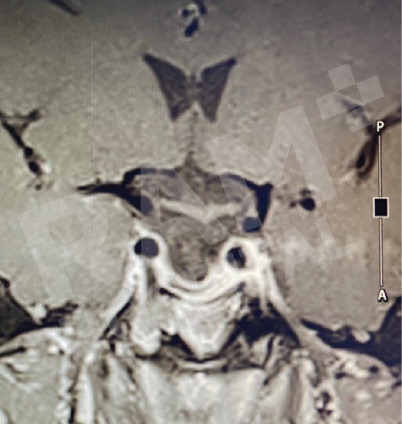

磁共振成像(MRI)可清晰、细致地显示垂体的异常病变,精准定位垂体腺瘤的位置;结合静脉造影增强检查,还能明确腺瘤的具体位置与病变性质,同时清晰呈现脑部周边组织及鼻窦的情况。这一项检查结果可为制定诊疗方案、随访评估垂体腺瘤的治疗效果,乃至规划手术方案提供明确、可靠的依据。